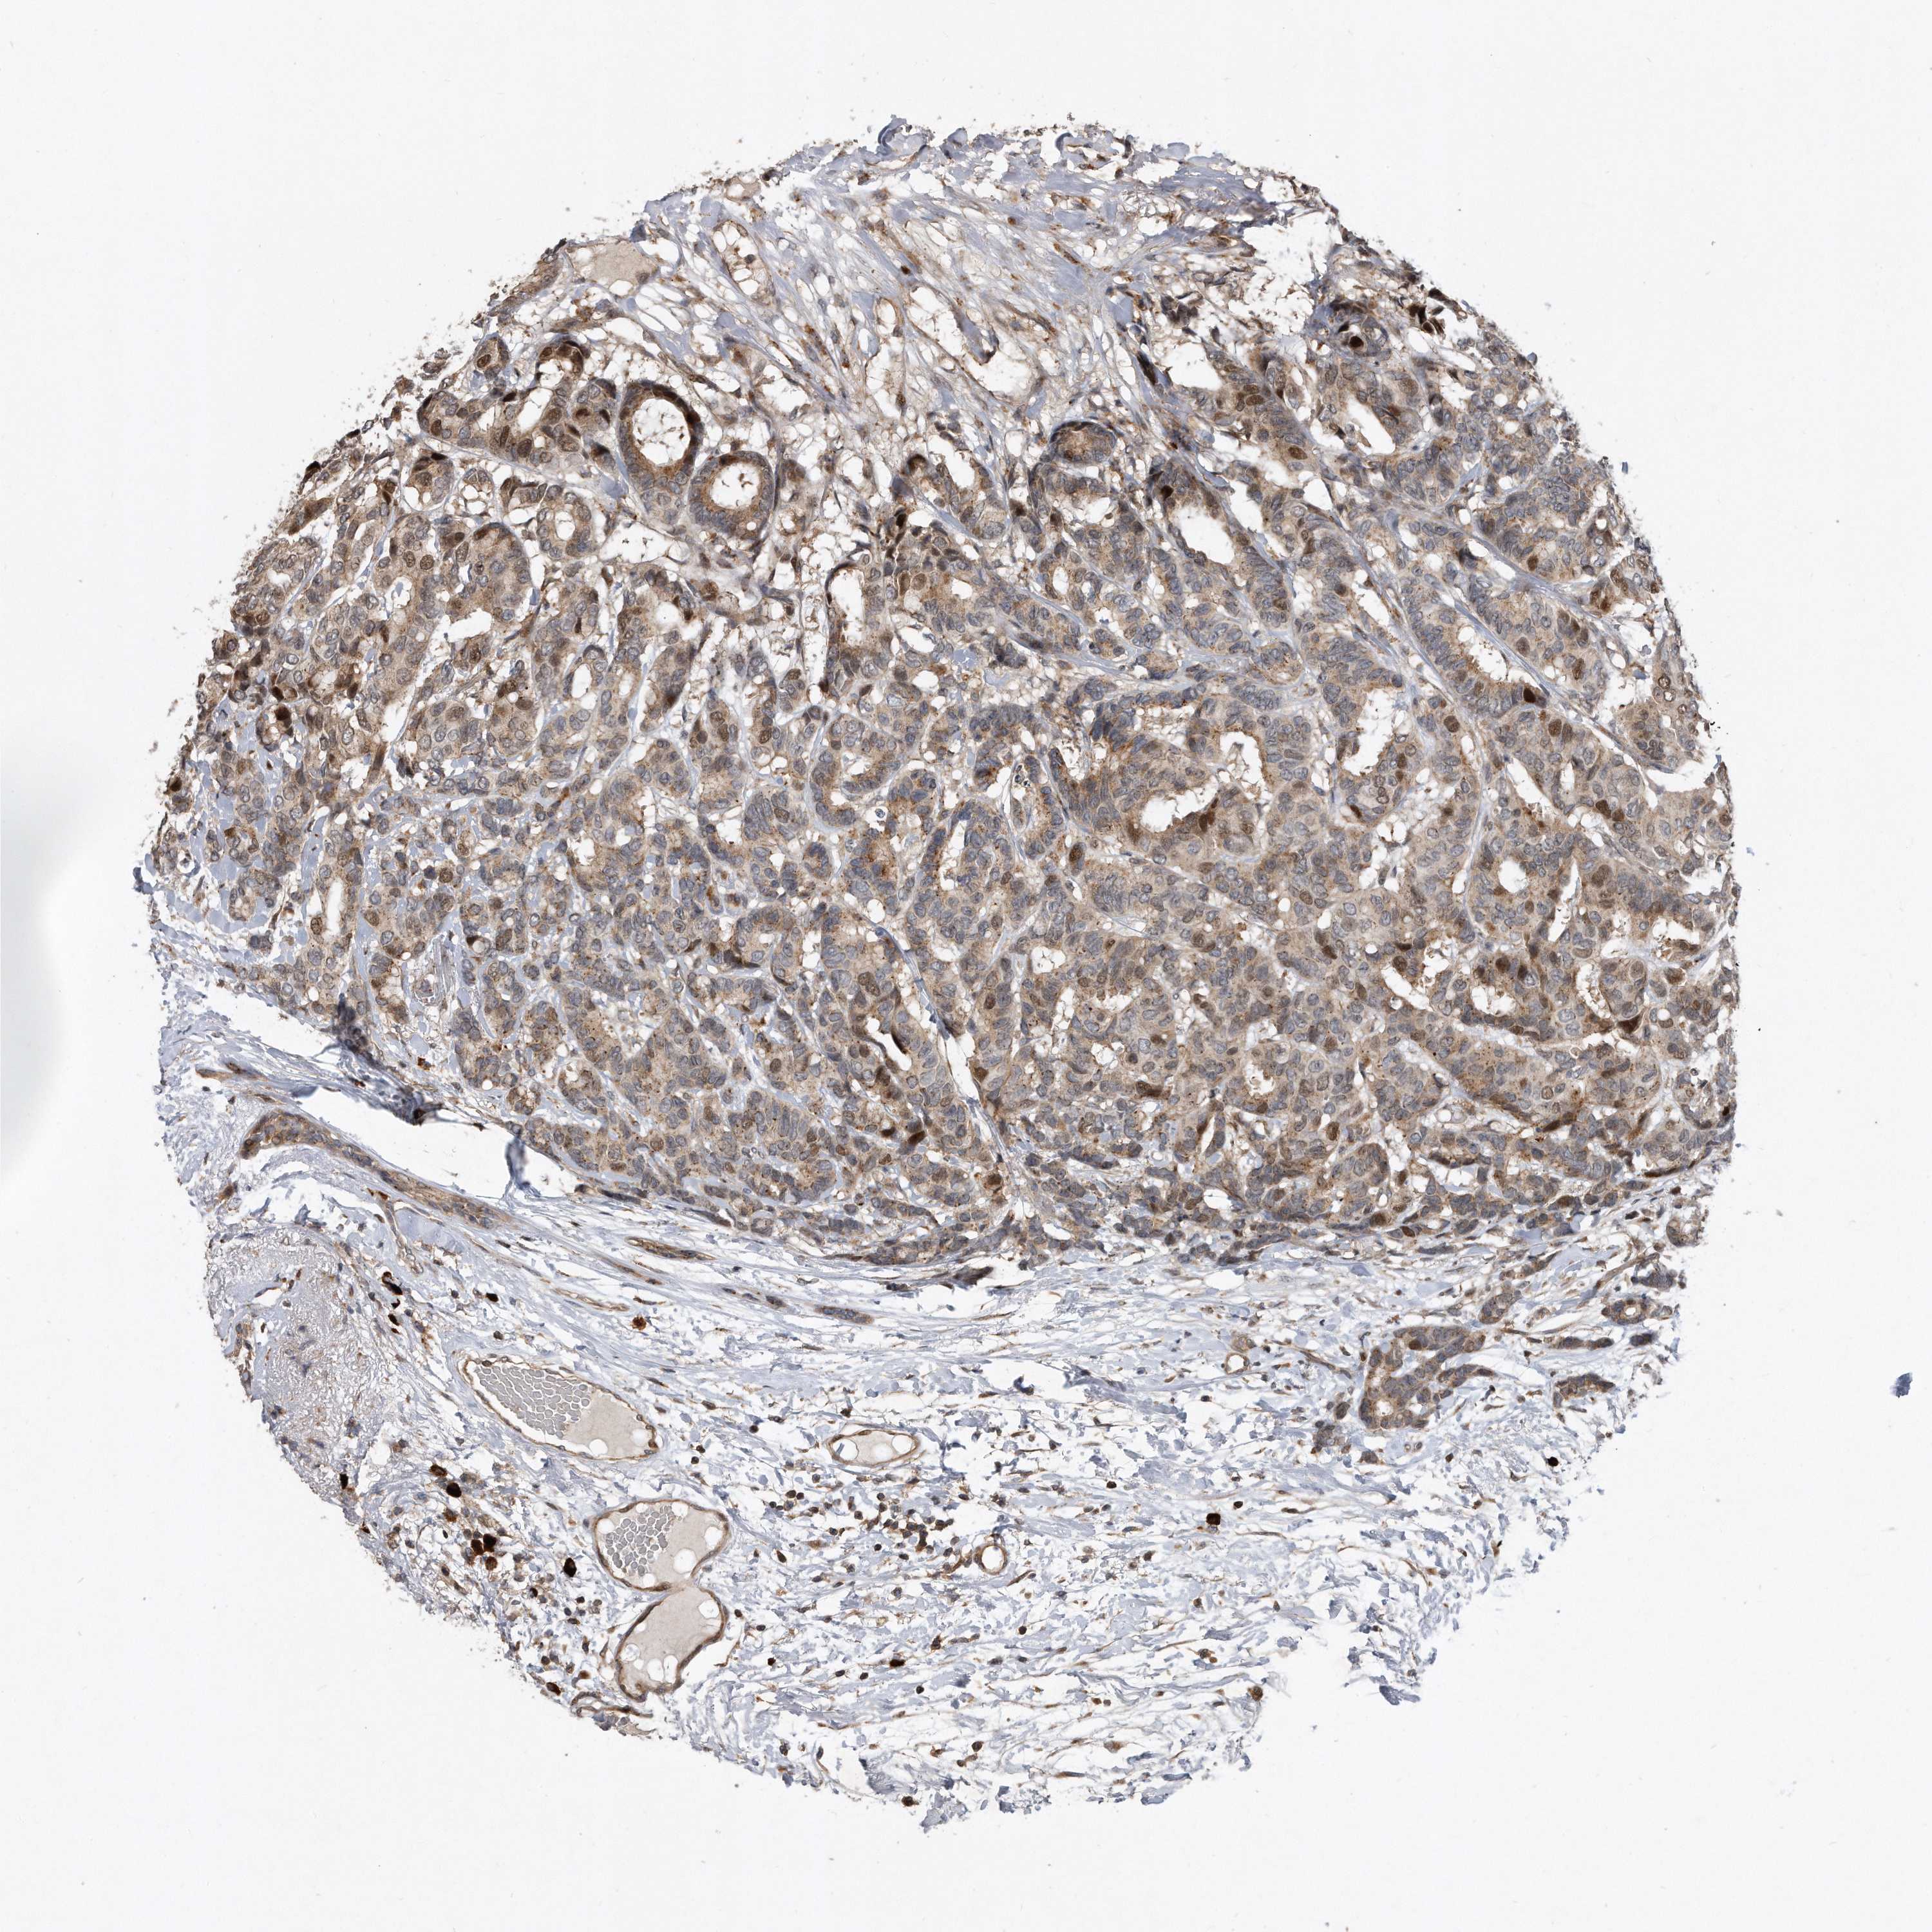

BRCA TCGA BRCA VALIDATION PROTEIN EXPRESSION

ANTIBODIES

AND

VALIDATION